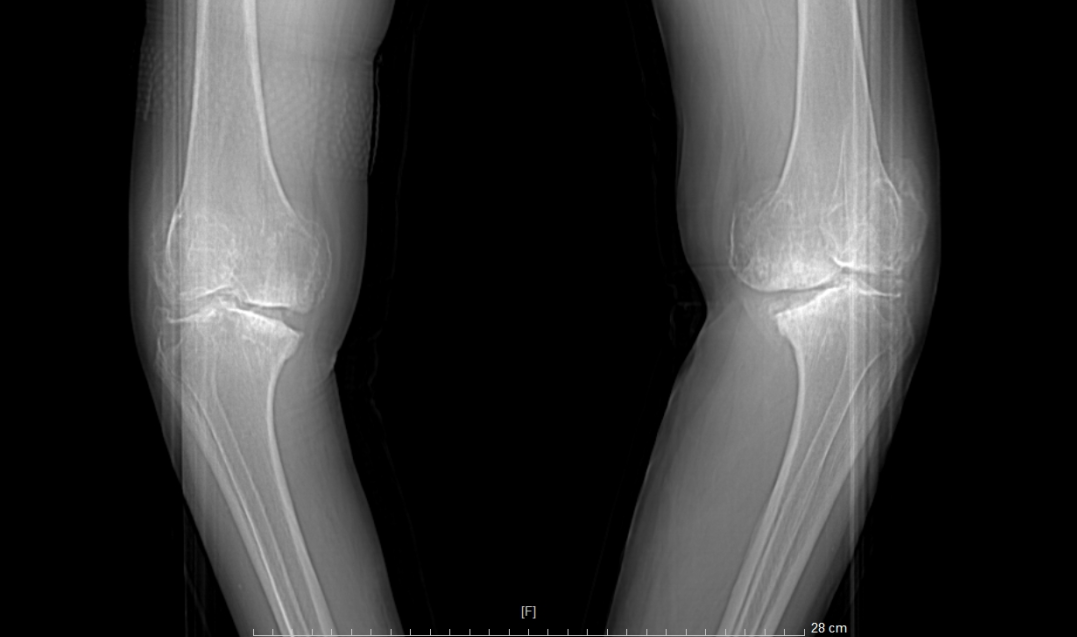

患者术后X光扫描

患者术前VS术后对比

①站立位X光片中显示关节间隙消失或极度狭窄